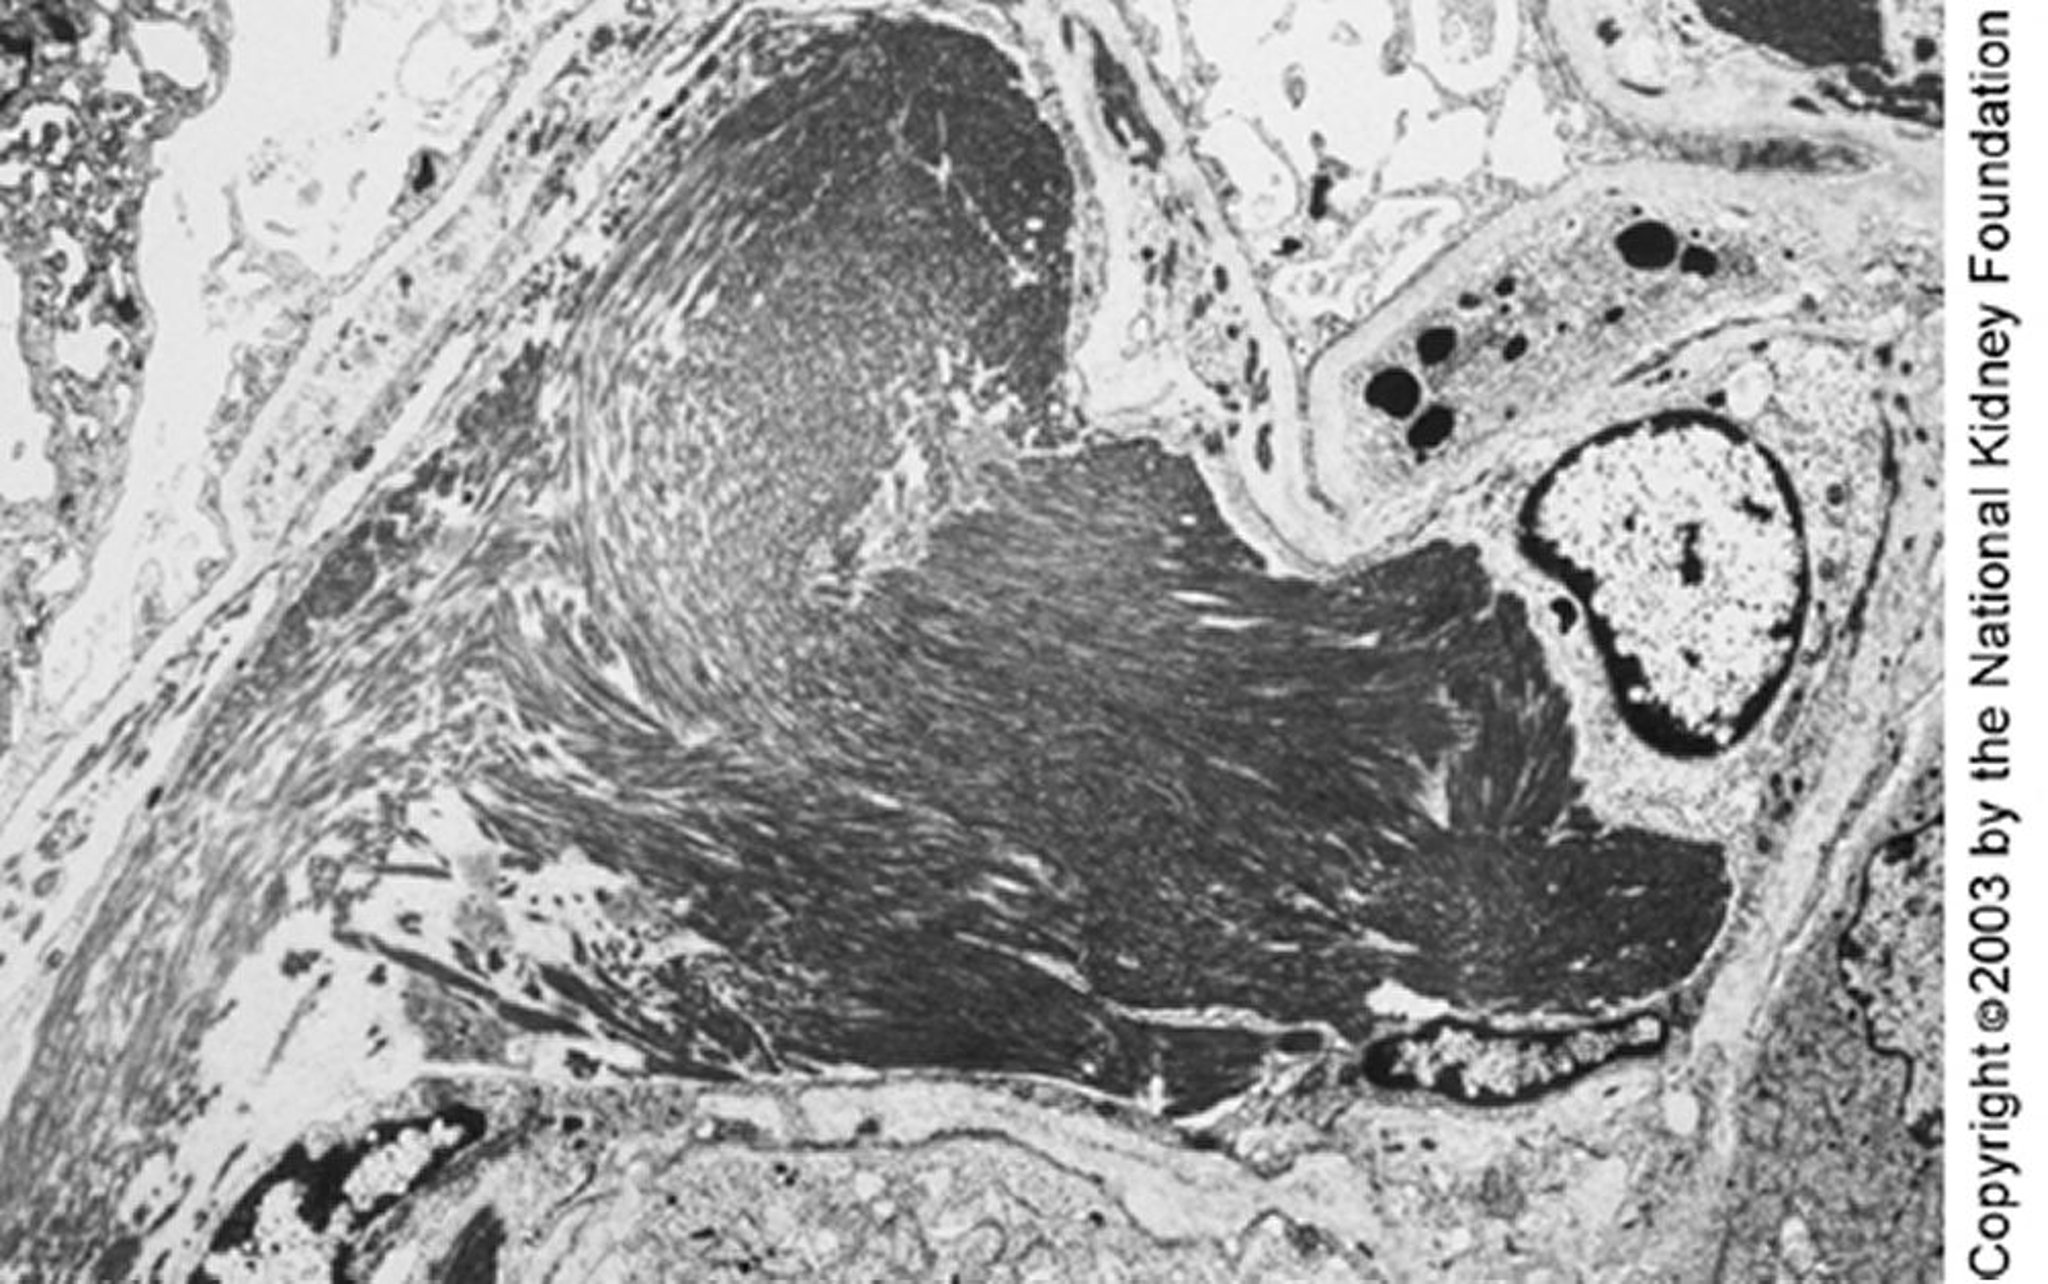

Glomerulopatía inmunotactoide

En la microscopia electrónica de transmisión pueden observarse microtúbulos grandes (de cerca de 50 nm de diámetro) organizados en ´formaciones paralelas. Los depósitos paralelos y la estructura microtubular pueden distinguir la glomerulopatía inmunotactoide de la glomerulopatía fibrilar (× 4000).

Image provided by Agnes Fogo, MD, and the American Journal of Kidney Diseases' Atlas of Renal Pathology (véase www.ajkd.org).